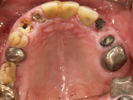

50代女性

![]() |

治療前 |

||

治療中。仮歯。 左上の奥にインプラント埋入。 噛みあわせ治療を行いました |

治療後 全体の歯で食事がおいしくできるようになったと喜んでおられました。 |